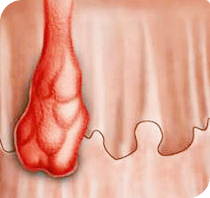

Sfortunatamente, le donne incinte, hanno spesso problemi con le

emorroidi. La cosa più pericolosa è che dopo il parto la

situazione può solo peggiorare. Dopotutto, senza la dovuta

attenzione al problema, la condizione delle pareti dei vasi

venosi peggiora solo. Durante la gravidanza, molti rimedi sono

controindicati a causa della loro composizione chimica

aggressiva. La gravidanza è già irta del verificarsi di molte

condizioni spiacevoli, il disagio delle emorroidi gonfie

aggiunge ancora più problemi alla futura mamma. In una